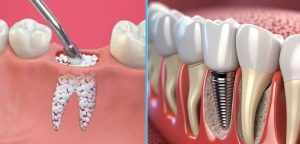

از دست رفتن دندان یکی از شایعترین مشکلاتی است که میتواند به دلایل مختلفی از جمله پوسیدگی شدید، بیماریهای پریودنتال، تروما، بیماری دیابت، افزایش سن و کشیدن سیگار رخ دهد. گفتنی است که از دست رفتن دندان در مردان بیش از زنان شایع است. پیامد این اتفاق نه تنها با از دست رفتن زیبایی و اختلال در عملکرد جویدن و تکلم همراه است بلکه باعث تحلیل تدریجی استخوان فک نیز میشود. ایمپلنتهای دندانی طی دهههای اخیر به عنوان یکی از موفقترینروشهای جایگزینی دندان از دسترفته مطرحشدهاند و به دلیل شباهت عملکردی و زیبایی شناختی با دندان طبیعی، استاندارد طلایی درمان محسوب میشوند. با این حال برای دستیابی به ثبات اولیه و موفقیت طولانی مدت ایمپلنت، وجود حجم و کیفیت کافی از استخوان فک لازم است.

در بسیاری از بیماران به ویژه در نواحی خلفی ماگزیلا یا پس از گذشت مدت طولانی از کشیدن دندان، شرایط ایدهآل استخوانی وجود ندارد. در چنین مواردی استفاده از پودراستخوانی به عنوان یکی از رایجترین و موثرترین روشهای بازسازی، امکان اصلاح نقایص استخوانی و ایجاد بستری مناسب برای کاشت ایمپلنت را فراهم میکند. در واقع این مواد با نقش کلیدی خود در فرآیندهای القای استخوانسازی Osteoconduction و هدایت استخوان سازی Osteoinduction جایگاه مهمی در پروتکلهای بازسازی بافت سخت در دندانپزشکی یافتهاند.

پودر استخوان (Bone Graft Powder)مادهای است که برای بازسازی و افزایش حجم استخوان آلوئولار مورد استفاده قرار میگیرد. این مواد میتوانند از منابع مختلف مانند خود بیمار، انسان دیگر، حیوان یا به صورت سنتتیک تهیه شوند که در ادامه به آنها خواهیم پرداخت. هدف اصلی این پودر ایجاد بستری یرای تشکیل استخوان جدید و فراهم کردن حجم کافی برای کاشت ایمپلنت یا بازسازی نقصهای استخوانی است.